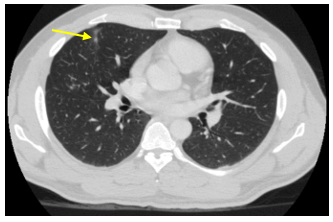

Chụp cắt lớp vi tính lồng ngực: Hình ảnh các nốt kính mờ rãnh liên thùy và màng phổi phải kích thước 2x3mm. Đám dải xẹp phổi thùy giữa phổi phải

Hình 6: Hình ảnh chụp cắt lớp vi tính lồng ngực: nốt tổn thương u phổi phải nhỏ hơn ban đầu sau 3 tháng điều trị (mũi tên vàng)